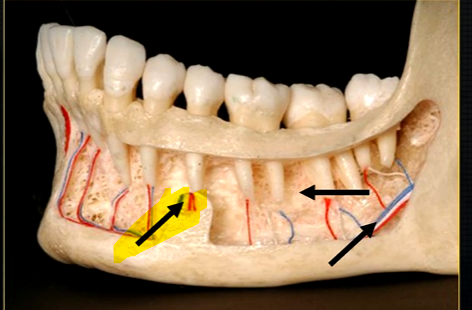

left hand side of the mandible buccal surface has been removed

roots of the teeth protrude in the underlying trabecular bone

inferior dental nerve

mental nerve - coming out of the mental foramen

reveals honeycombed pattern of trabecular bone

dense outline of the individual sockets of the teeth

cortical bone which forms the lower border

can see honeycombed pattern

mental foramen - black radiolucency - near 1st and 2nd premolars

sockets of the teeth are represented by thin, white, opaque lines → ‘ lamina dura’

dense, white, radiopaque line → dense bone of mylohyoid ridge

underneath mylohyoid ridge - looks more radiolucent → this is due to the lingual indentation of submandibular fossa

dense cortical bone of the lower border

radiolucent shadow created by the lingual pit

lower occlusal

small bony spurs of the genial tubercles